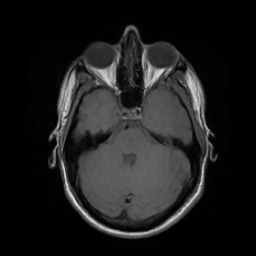

Motion artifacts are a primary source of magnetic resonance (MR) image quality deterioration with strong repercussions on diagnostic performance. Currently, MR motion correction is carried out either prospectively, with the help of motion tracking systems, or retrospectively by mainly utilizing computationally expensive iterative algorithms. In this paper, we utilize a novel adversarial framework, titled MedGAN, for the joint retrospective correction of rigid and non-rigid motion artifacts in different body regions and without the need for a reference image. MedGAN utilizes a unique combination of non-adversarial losses and a novel generator architecture to capture the textures and fine-detailed structures of the desired artifacts-free MR images. Quantitative and qualitative comparisons with other adversarial techniques have illustrated the proposed model's superior performance.